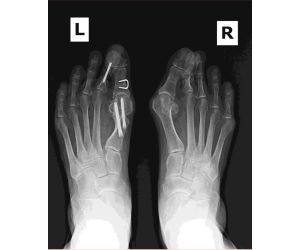

1 or 2 Screw Fixation for MIS Bunions?

Bradley P. Abicht, DPM, FACFAS

Would you jump from a plane with only one parachute & no reserve parachute?! Not me. Similarly, I’m traditionally a 2-screw fixation surgeon for...